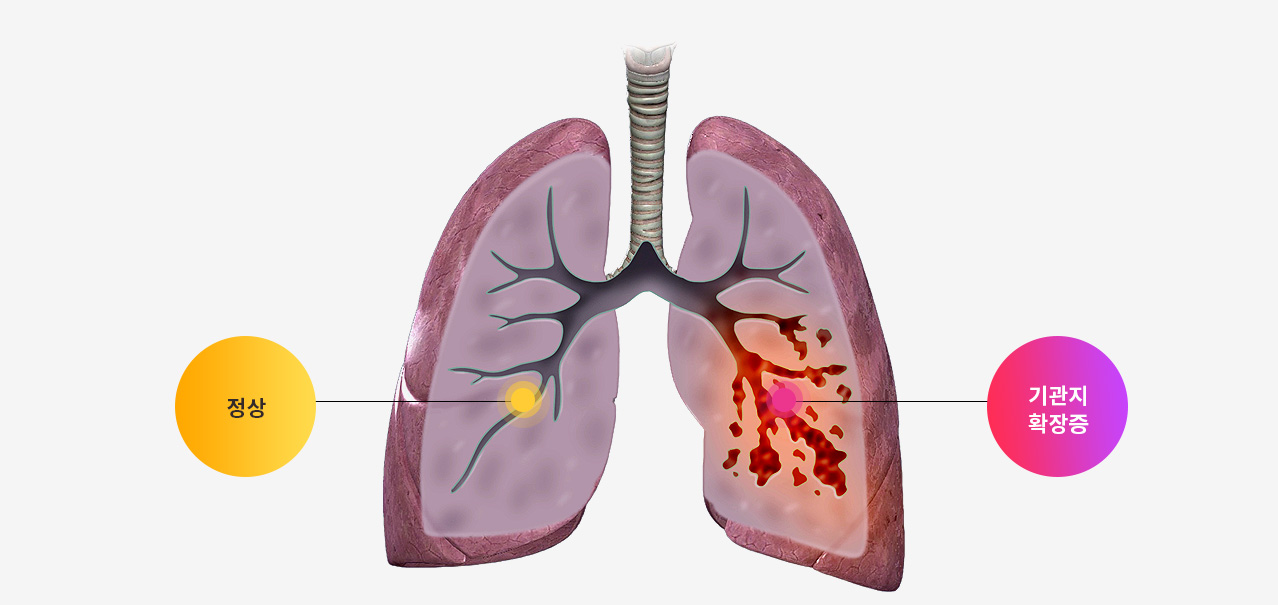

기관지확장증이란?

​기관지벽의 근육 및 탄력 성분의 파괴로 인해 기관지가 비정상적으로 늘어나 여러가지 문제를 일으키는 질환을 말합니다.

확장된 기관지 내부에는 가래가 고이게 되는데 기관지가 손상되어 있는 상황이므로 잘 빠져나가지 못하게 되고 이로 인해 쉽게 감염되고 그러면서 기관지 벽이 약해집니다. 이렇게 되면 기관지가 쉽게 파괴되고 다시 가래가 증가되는 악순환이 형성됩니다.